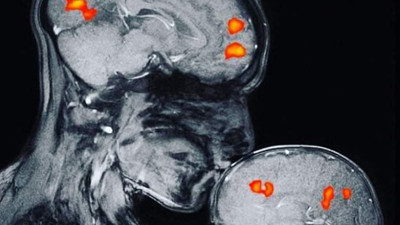

Asma yaprağı toplarken yılan saldırdı. Konuşmasını bile etkiledi Artvin’de bir kadın, bahçede asma yaprağı toplarken yılan tarafından ısırıldı. Solunum cihazından ayrılan hastanın konuşma problemi saptanması üzerine, beyin MRG (manyetik rezonans görüntüleme) alındı ve beynine pıhtı attığı saptandığı bildirildi.